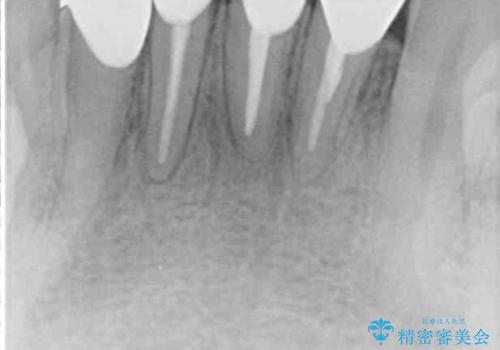

- 下の前歯がすり減って、痛みがあるとのことで来院された患者様です。

咬合力が強く、4本のうち3本の歯が失活しており、腫れや痛みが認められました。

3歯に根管治療を行い、その後4歯をオールセラミッククラウンにて補綴することとしました。

根管治療により腫れと痛みが引き、叢生の認められた歯列は補綴治療により改善され、清掃性が増しました。